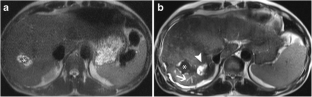

Fig. 2